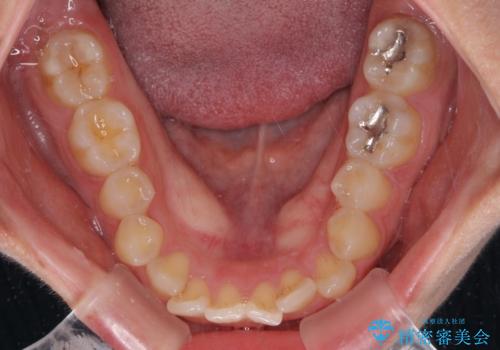

- 左右の八重歯を気にして来院された患者様です。

舌の突出癖により上下前歯が開咬となりましたが、舌のトレーニングと顎間ゴムの使用により、元々の被蓋関係に改善することができました。